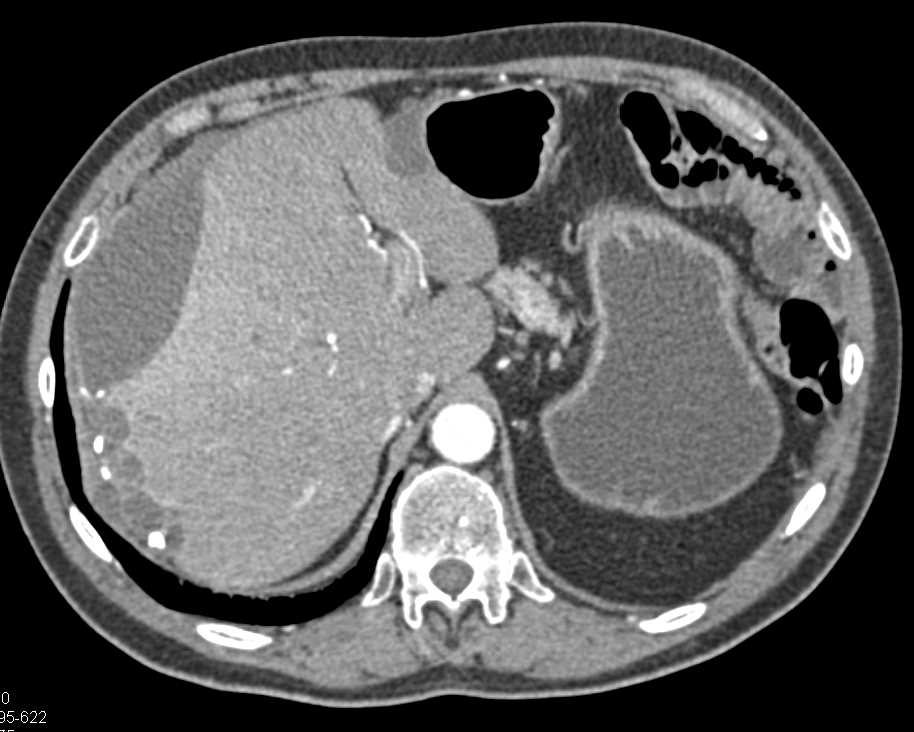

Pseudomyxoma Peritonei (PMP) with Scalloping of the Liver Surface